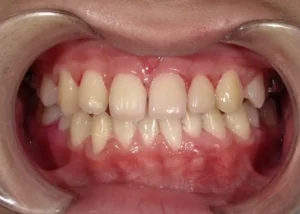

正面

- After

- 診断名

- 反対咬合(※一期治療のみ)

- 治療期間・通院回数

- 約9ヶ月・8回

- 矯正装置

咬合挙上床

リンガルアーチ

上顎前方牽引装置- 総費用